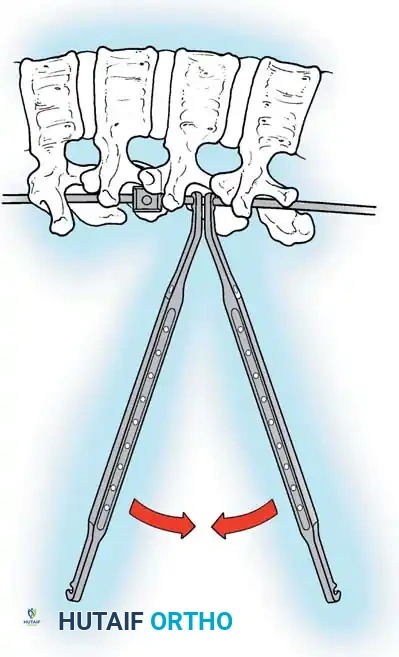

The Moe Technique (Thoracic Spine)

The Moe technique is a highly effective method for achieving intra-articular arthrodesis in the coronally oriented thoracic facet joints.

Fig. 38-26: The Moe technique of thoracic facet fusion, demonstrating the creation of hinged bone flaps.

- Expose the spine fully to the tips of the transverse processes.

- Using a sharp osteotome or Cobb gouge, begin a cut over the cephalad articular process at the base of the lamina.

- Carry this cut along the transverse process almost to its tip. Bend this cortical fragment laterally so it lies between the transverse processes, ideally leaving it hinged on its lateral periosteal attachment to preserve local vascularity.

- Thoroughly denude all articular cartilage from the superior articular process using a sharp curet.

- Make a secondary cut in the superior articular facet, working medially to laterally, producing another hinged fragment.

- Pack the resulting intra-articular defect tightly with cancellous bone graft.